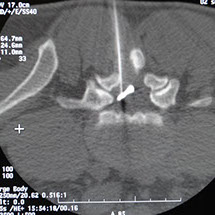

Le radio-guidage, par scopie ou par scanner améliore la précision de l’injection, notamment dans les régions profondes (rachis…), permet de choisir le bon point d’entrée de l’aiguille et de suivre son trajet.

Ce premier temps permet de vérifier le bon positionnement de l’aiguille dans l’articulation à traiter.